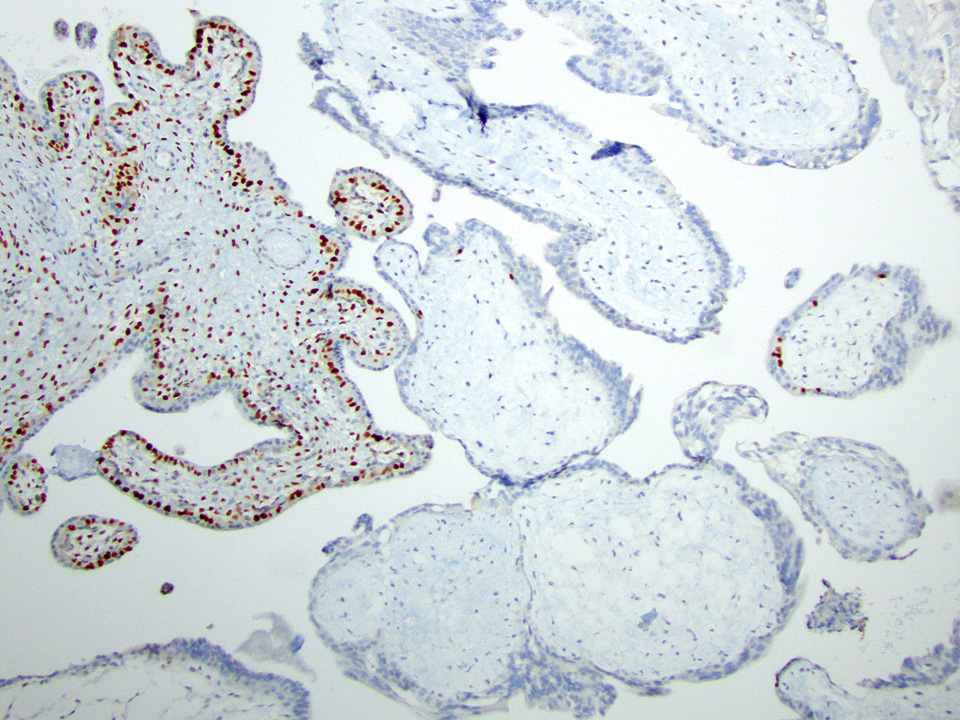

Microscopic (histologic) images

Contributed by Chrystalle Katte Carreon, M.D. and Drucilla J. Roberts, M.D.

- Loss of the normal nuclear p57 staining in cytotrophoblasts and villous stromal cells; therefore, p57 immunostain is often helpful in distinguishing complete mole (absence of the normal pattern of staining in chorionic villi) versus edematous villi (normal pattern of staining with nuclear staining in villous cytotrophoblasts and stromal cells

- Retained normal p57 staining pattern; therefore, p57 immunostain will not distinguish a partial hydatidiform mole from a nonmolar gestation